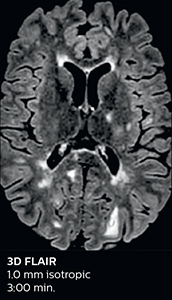

3D FLAIR (with Compressed SENSE)

3D FLAIR

1.0 x 1.0 x 1.0 mm*

2:50 min.